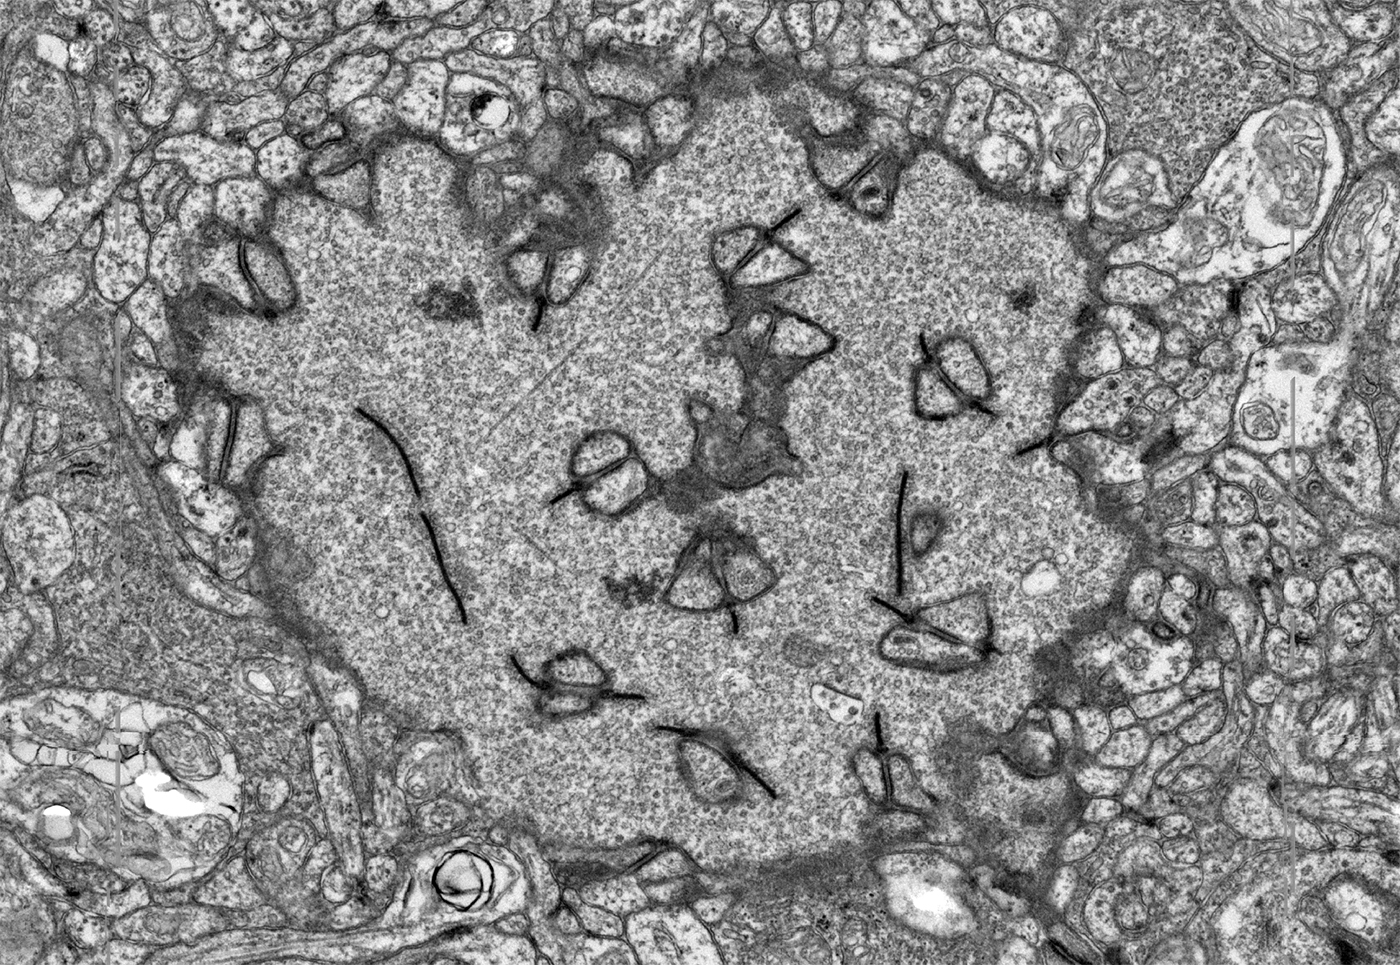

Photoreceptor Cilium Tilt Series